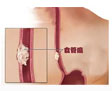

冠状动脉粥样硬化性心脏病

疾病介绍:冠状动脉粥样硬化性心脏病是冠状动脉血管发生动脉粥样硬化病变而引起血管腔狭窄或阻塞,造成心肌缺血、缺氧或坏死而导致的心脏病,常常被称为“冠心病…【详细】